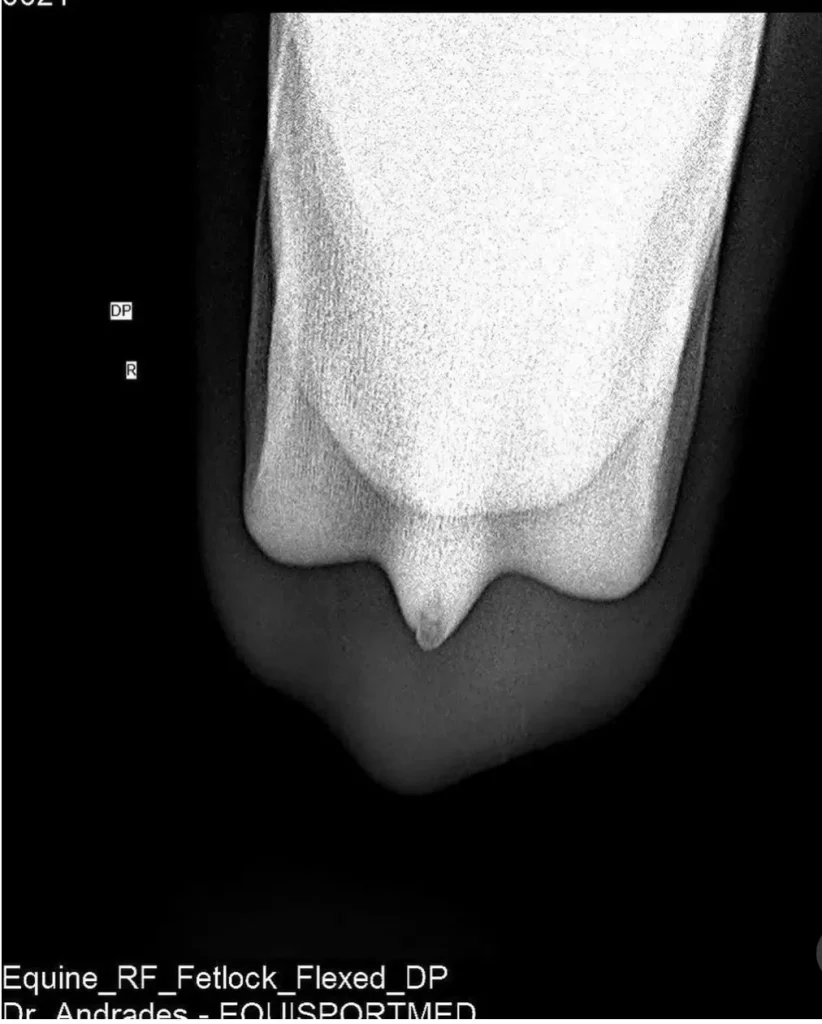

Advanced Diagnostic Imaging

We carry out diagnostic tests such as scintigraphy, magnetic resonance imaging, among others, in collaboration with equine veterinary hospitals.